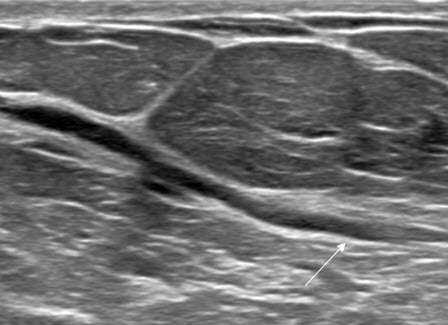

Case: Breast Ductal Anatomy and Function Figure 1

Figure 1: Ultrasound demonstrating benign retroareolar duct ectasia